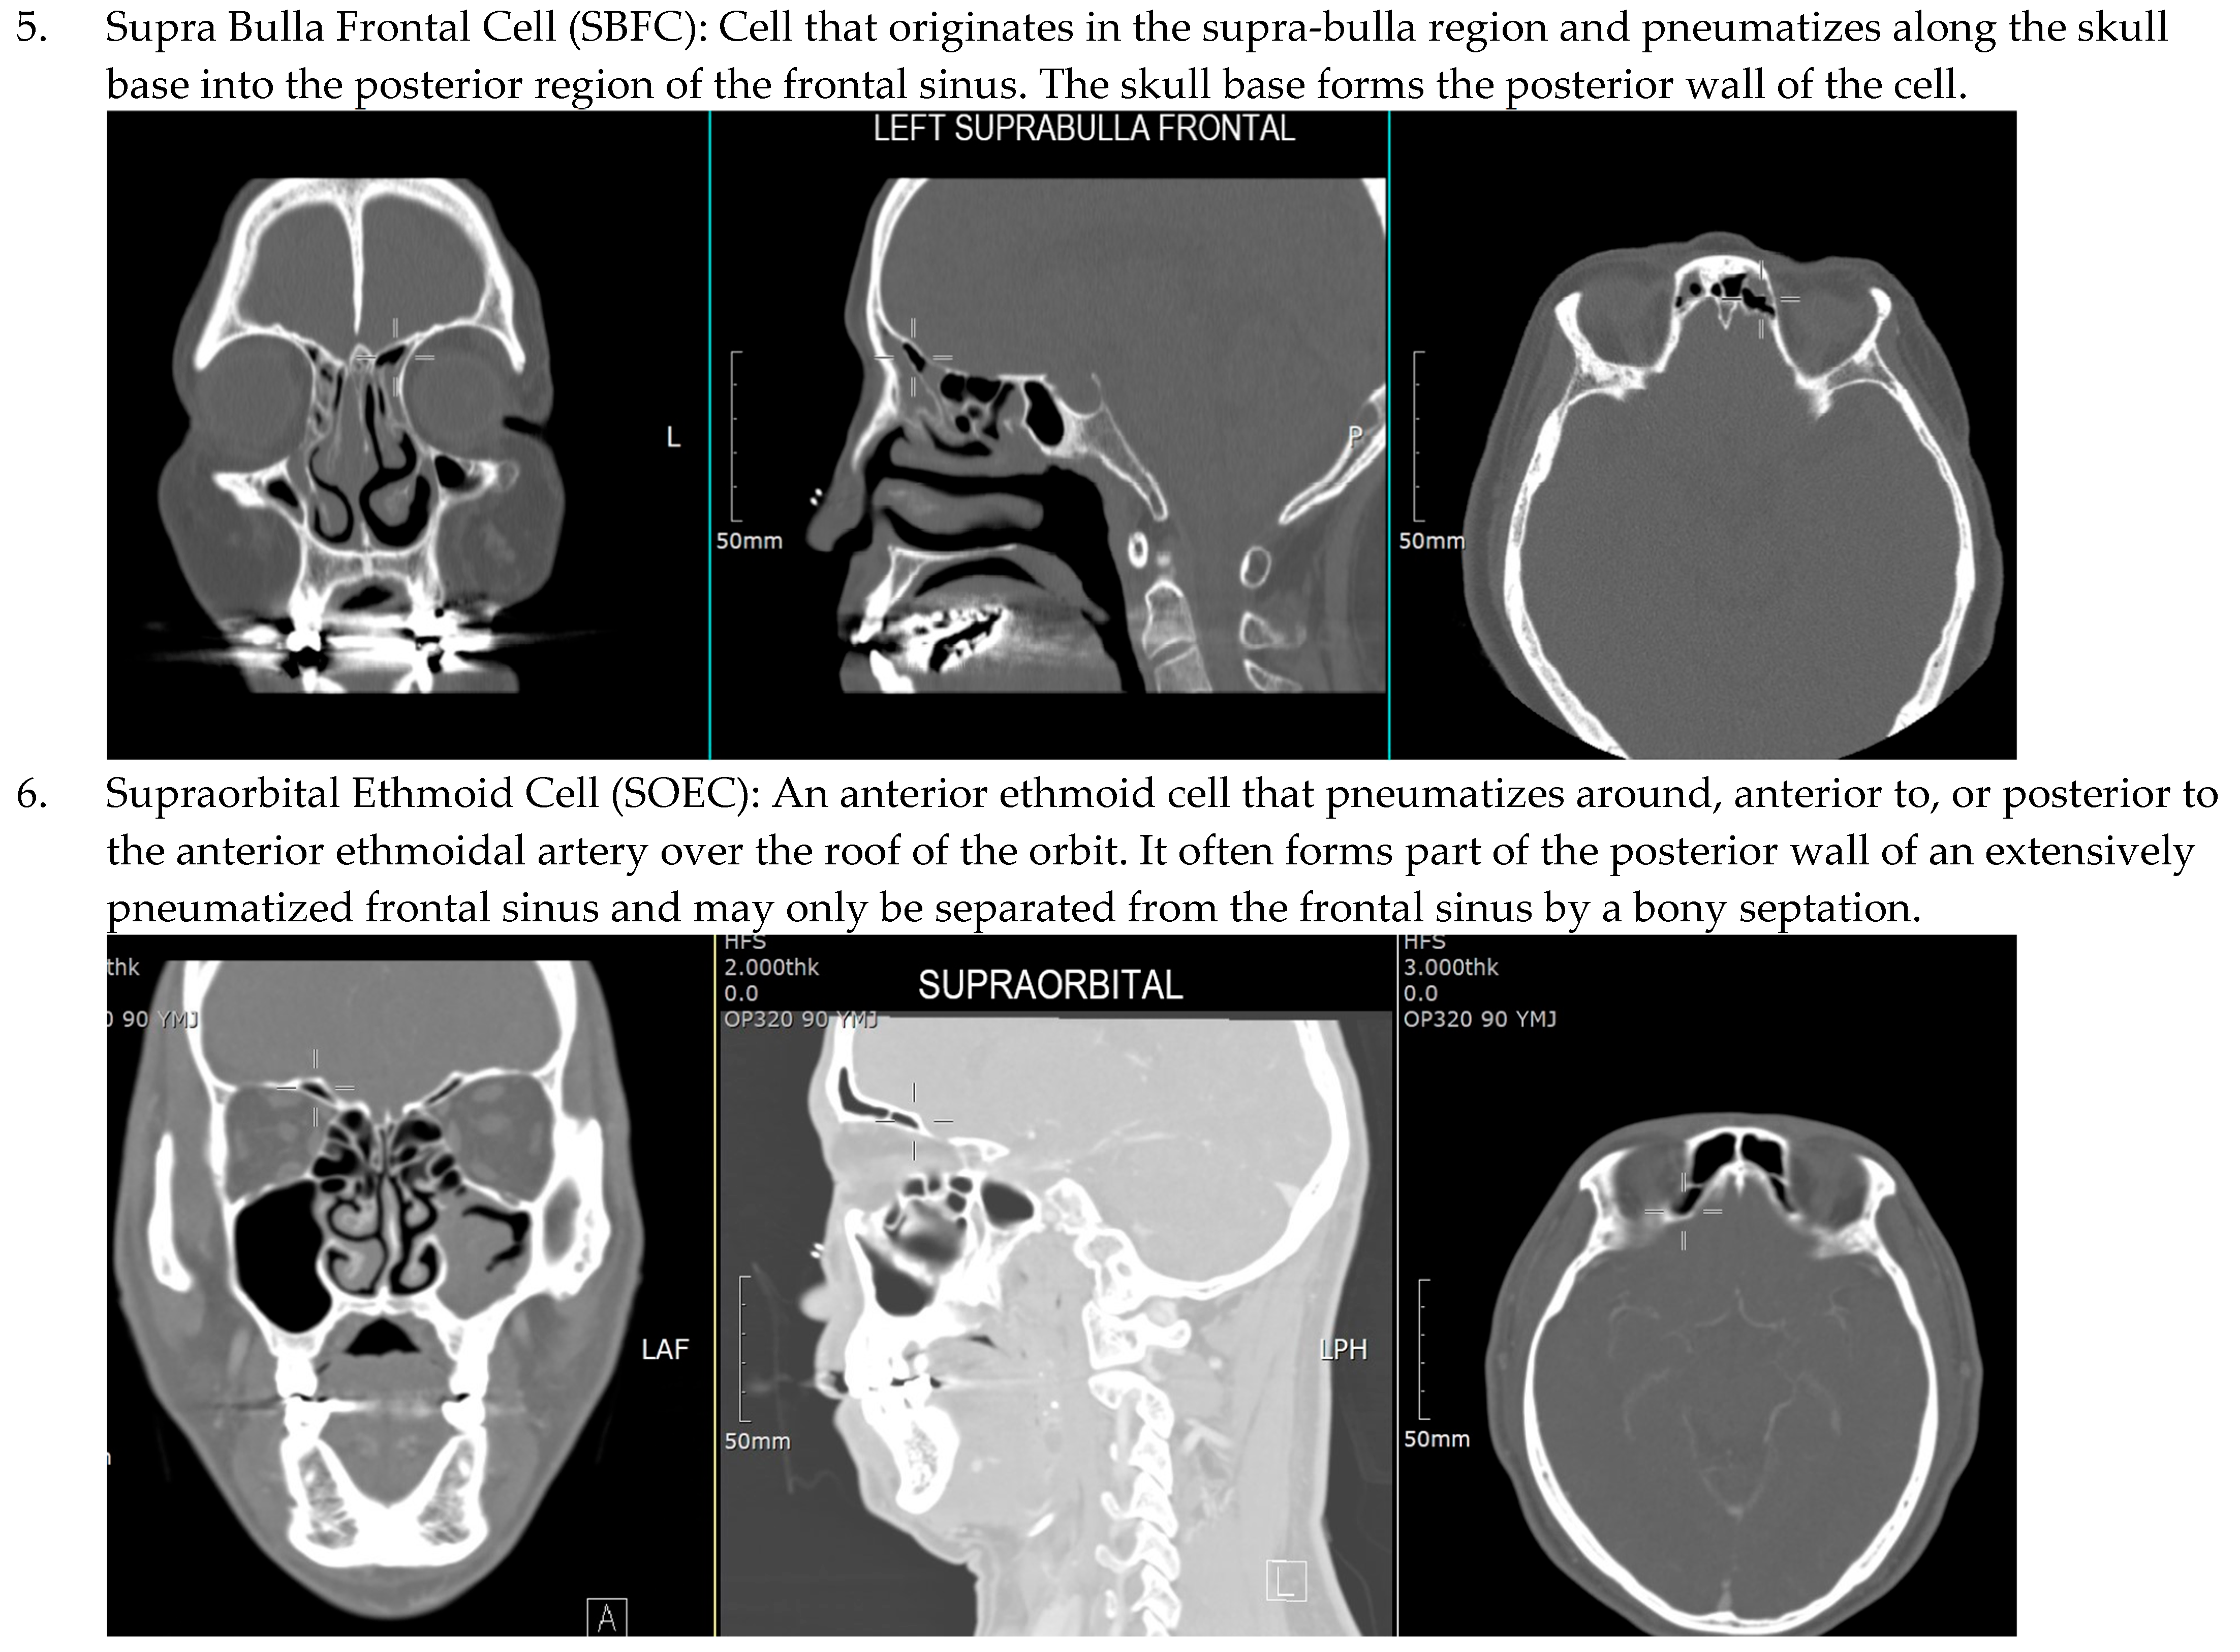

3. Results

3.1. Demographic Data